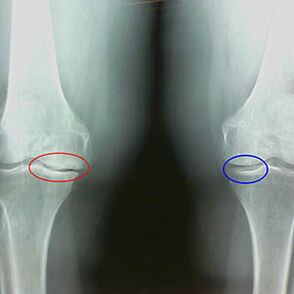

Early X -Ray characteristics of the second phase of knee arthrosis:

- The pointed edges of the tubercles between -are described in the tibi, where the cross -shaped ligament attached;

- narrowing of the common gap on the medial side;

- The highlighted ends of bone conditions on the sides of the media, less frequently in lateral - depending on the development of valgus deformity or variable joint.

For the second stage in LarsenThe narrowing of the common gap by more than 50% is characteristic, but this can only be controlled in dynamics or compared to a different union.

Radiography indicates the presence of osteophytes, a difference in the space between the femur and tibia bones, which indicates the loss of knee cartilage.Sometimes X radiation of the knee joints shows significant signs of cartilage coating, but patients do not suffer significant pain.On the contrary, the first phase arthrosis may disrupt the knee function, as the cause of the pain is the hypotonic muscles.